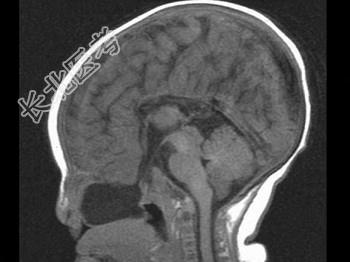

- 单项选择题两个月女婴,口咽部有一肿块, 行CT检查如图,请选择最可能的诊断 ( )

A、脑积水

B、胼胝体发育不全

C、透明隔囊肿

D、前脑无裂畸形

E、Dandy-Walker综合征